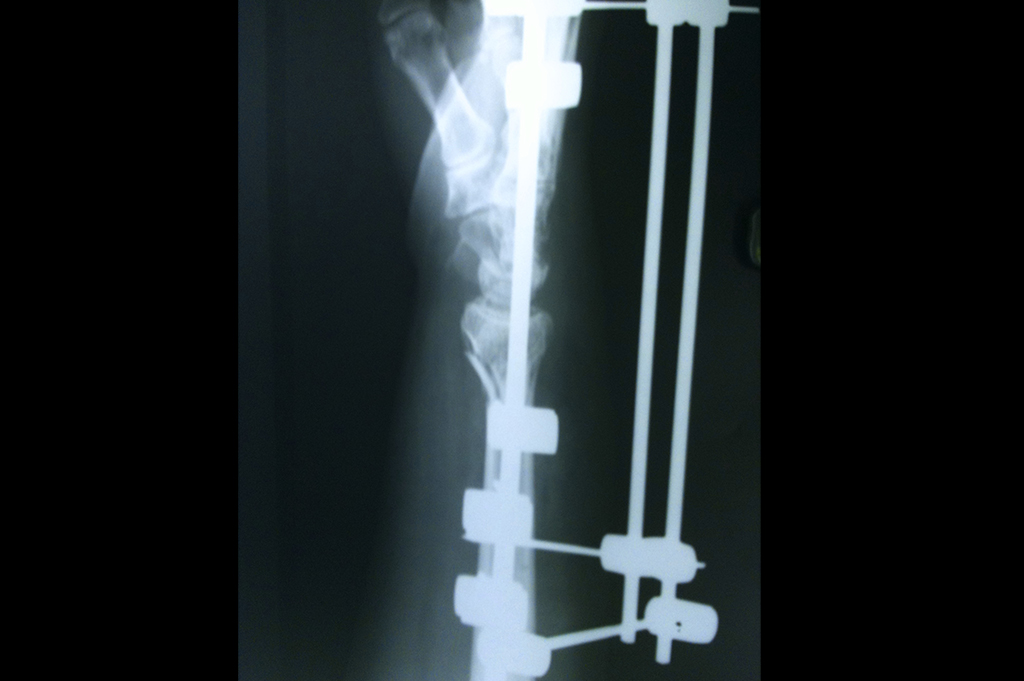

Subtrochanteric Fracture